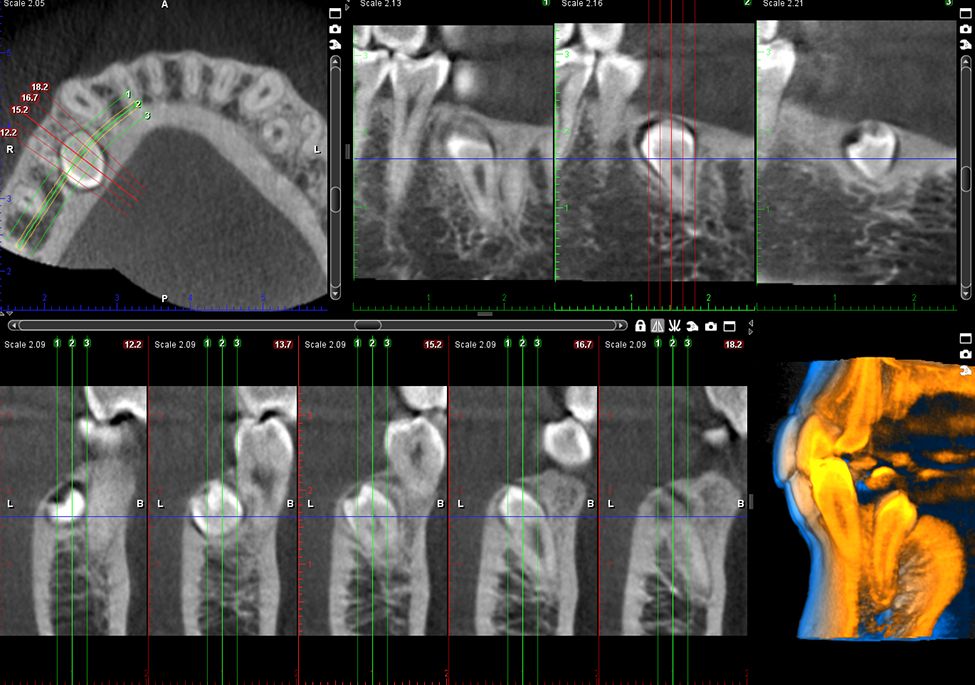

Obrazy Kliniczne Planmeca ProMax 3D s

Specjalny tryb obrazowania endodontycznego pozwala na tworzenie szczegółowych, trójwymiarowych zdjęć. Woksele o rozdzielczości 75 μm zapewniają wyjątkową jakość obrazu, uwzględniając nawet najdrobniejsze detale.

Oprogramowanie Planmeca Romexis® oferuje kompleksowe narzędzia do obrazowania przeznaczone dla wszystkich klinik – niezależnie od ich wielkości. Jest to jedyne oprogramowanie stomatologiczne na rynku, które łączy w sobie wszystkie funkcje obrazowania z kompletnym systemem CAD/CAM.